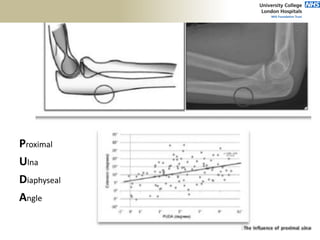

Proximal

Ulna

Diaphyseal

Angle